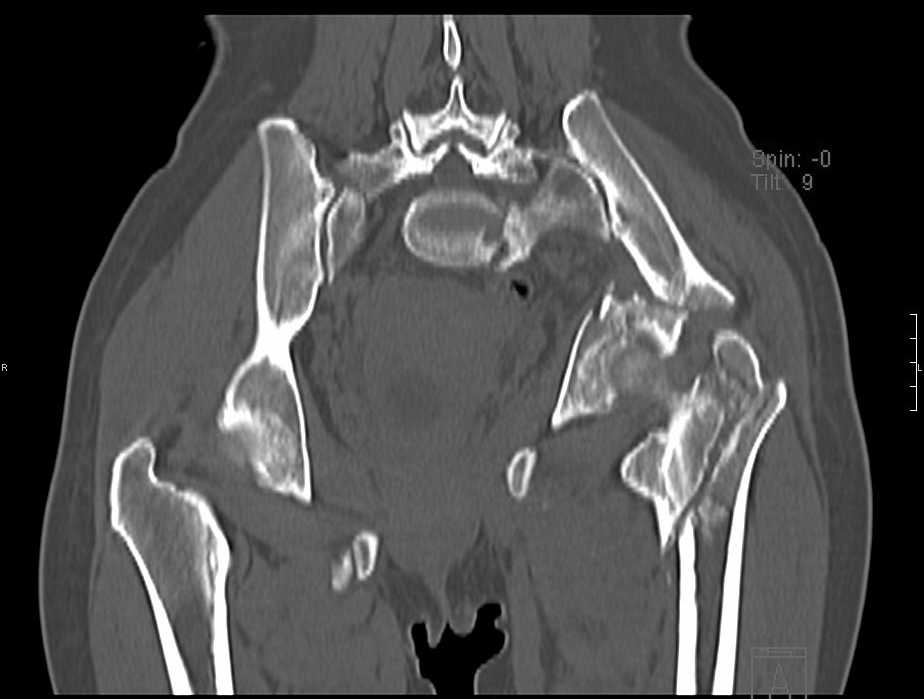

Больная 43 года (промышленный альпинист), 28.07.08 в результате падения с 5 этажа получила политравму: Перелом свода и основания черепа. Вертикально-нестабильное повреждение таза, осложнённое разрывом мочевого пузыря. Чрезвертельный перелом левого бедра. Перелом правой таранной кости, переломовывих правой кубовидной кости. Тупая травма живота, разрыв печени, ушиб почек. Забрюшинная гематома. В день травмы - лапаротомия, ушивание ран печени. Разрыв мочевого пузыря не диагностирован. Течение болезни осложнилось развитием мочевого затёка и обширной пред- и забрюшинной флегмоны, сформировался свищ мочевого пузыря. 19.8.2008 вскрытие, дренировние флегмоны, ревизия мочевого пузыря, обтурация мочевого свища (свищ закрылся в октябре), 1.10.2008 некрэктомия, пластика по Шеде-Лидскому правой кубовидной кости. По результатам КТ диагностирован рак правой почки (диагностическая находка), 8.10.2008 нефрэктомия справа. Переломы велись консервативно. Имеется вертикальное смещение левой половины таза с выраженным отведением крыла (клинически подвижности нет), несросшийся низкий двухколонный перелом левой вертлужной впадины с потерей конгруэнтности, укорочение около5 см, застарелый разрыв лонного сочленения, неправильно сросшиеся переломы обеих ветвей правой лонной кости с укорочением, патологическая подвижность лоно-седалищного фрагмента слева. Правая нижняя конечность неопорна, несмотря на то, что лежа прямую ногу поднимает, ходит на левой ноге (ортопедическая обувь) с костылями, справа тазобедренный ортез. Седалищные нервы работают.Урологи отпустили больную на 6 мес.

с большей вероятностью пациентка придет к эндопротезированию тазобедренного сустава, поэтому необходимо создать надежную "опору" сзади и подготовить бедро к имплантации любой классической ножки.ИМО бедренной кости GN, АНФ на таз,по необходимости остеотомия крестца, восстановление конфигурации задних отделов и устранение вертикального смещения половины таза. дождаться сращения крестца и бедренной кости. второй этап эндопротезирование: ножка цвай-мюллер или спаторно,ацетабулярно онкологическое антипротрузионное кольцо левое либо ацетабулярный компонент по индивидуальным параметрам для протезирования после резекции лонной седалищной костей и вертлужной впадины при онкопатологии. в кольцо пару трения металл\металл с цементной чашкой IMPLANTCAST, т.к. пациентка молодая.лонные кости можно оставить в покое, какой никакой рубец есть. с уважением Сергей.